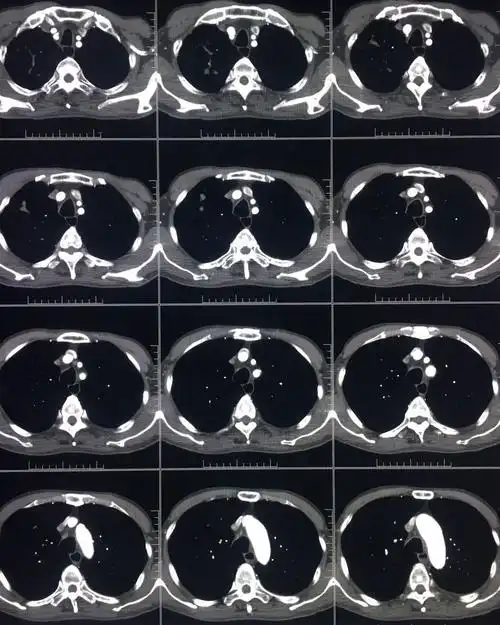

胸部ct平扫图片金典

图片是患者ct平扫和多期增强扫描(动脉期,静脉期,平衡期或延迟期)的